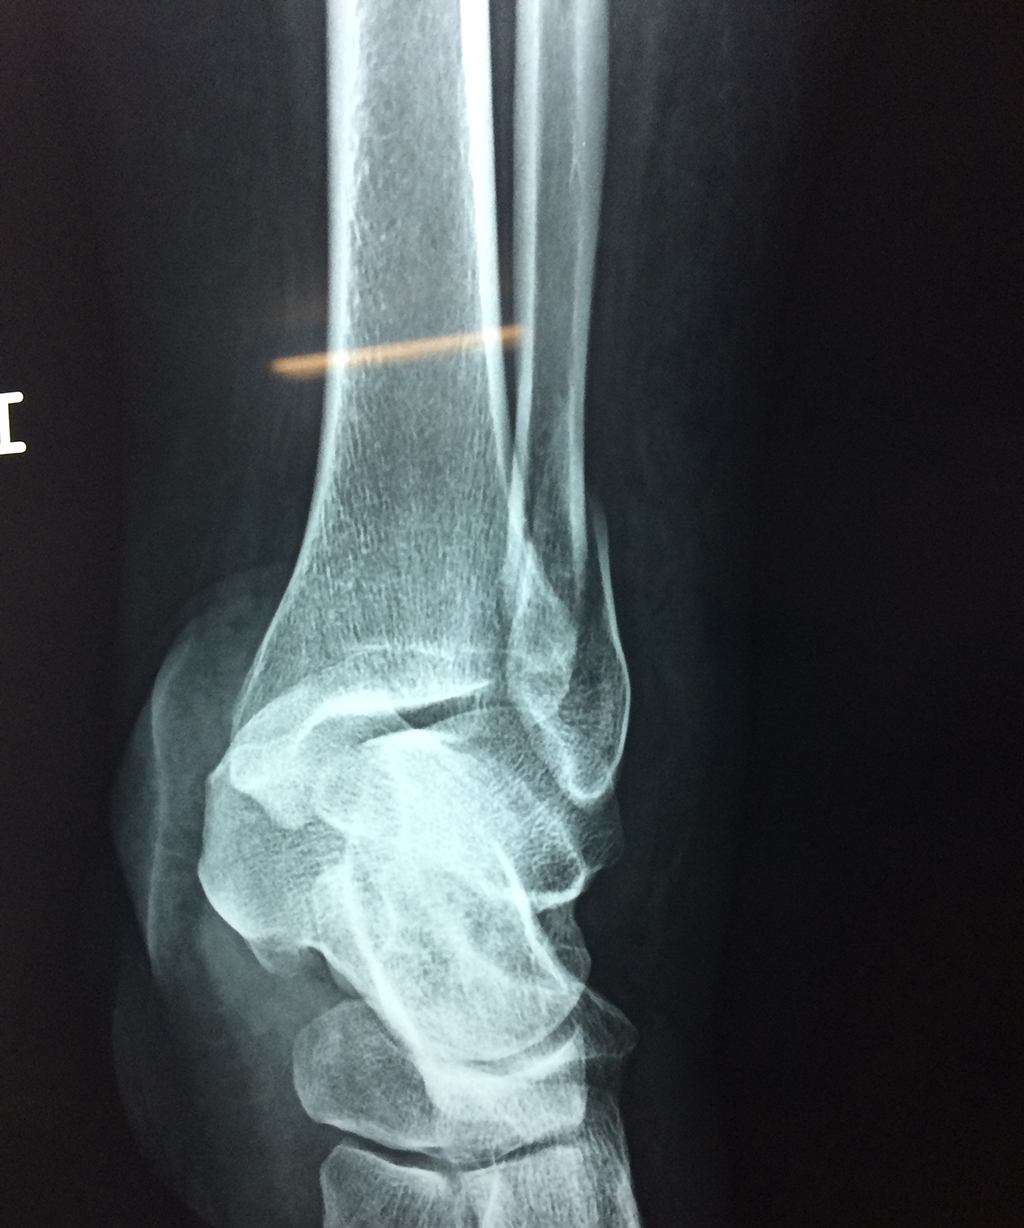

Una fractura de tobillo es la rotura de uno o más de los huesos del tobillo. Estas fracturas pueden ser:

- Parciales (el hueso está sólo parcialmente fisurado, no del todo).

- Completas (el hueso está perforado y está en 2 partes).

- Producirse en uno o ambos lados del tobillo.

- Los extremos de los huesos están desalineados entre sí (desplazados).

- La fractura se extiende hasta la articulación del tobillo (fractura intra-articular).